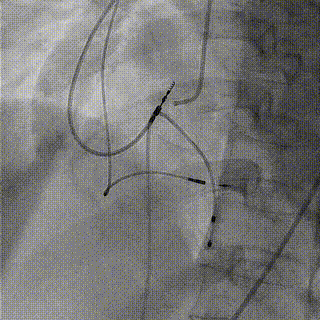

手术过程

1.LAD+LCX造影

2.右冠造影

3.主动脉根部造影

4.18mm球囊预扩

5.跨弓+跨瓣

6.释放至工作位

7.完全释放

8.术后造影,冠脉血流通畅

瓣膜释放后,复查左室-主动脉瓣峰值压差0-1mmHg,食道超声及造影像均提示瓣膜无反流,冠脉血流通畅。

术中影像

1.主动脉根部造影,可见大量反流

2.输送系统过主动脉弓

3.输送系统造影定位

4.释放瓣膜

5.瓣膜完全释放

6.最终造影,反流消失